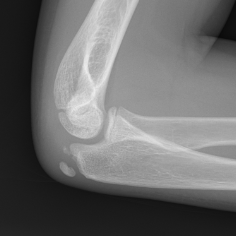

Closure

Capitellum / trochlea / lateral epicondyle

- fuse together age 14

- fuses to metaphysis age 15

Medial epicondyle fuses age 15 girls and 17 in boys